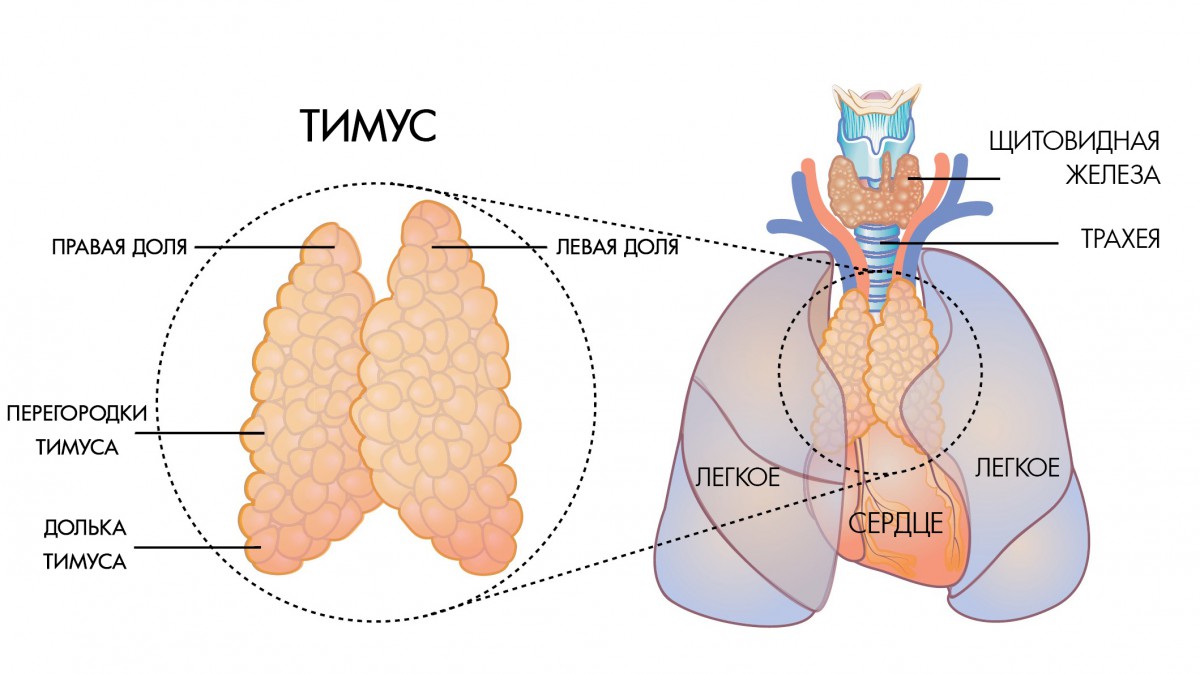

Фотографии вилочковой железы тимуса: структура и функции